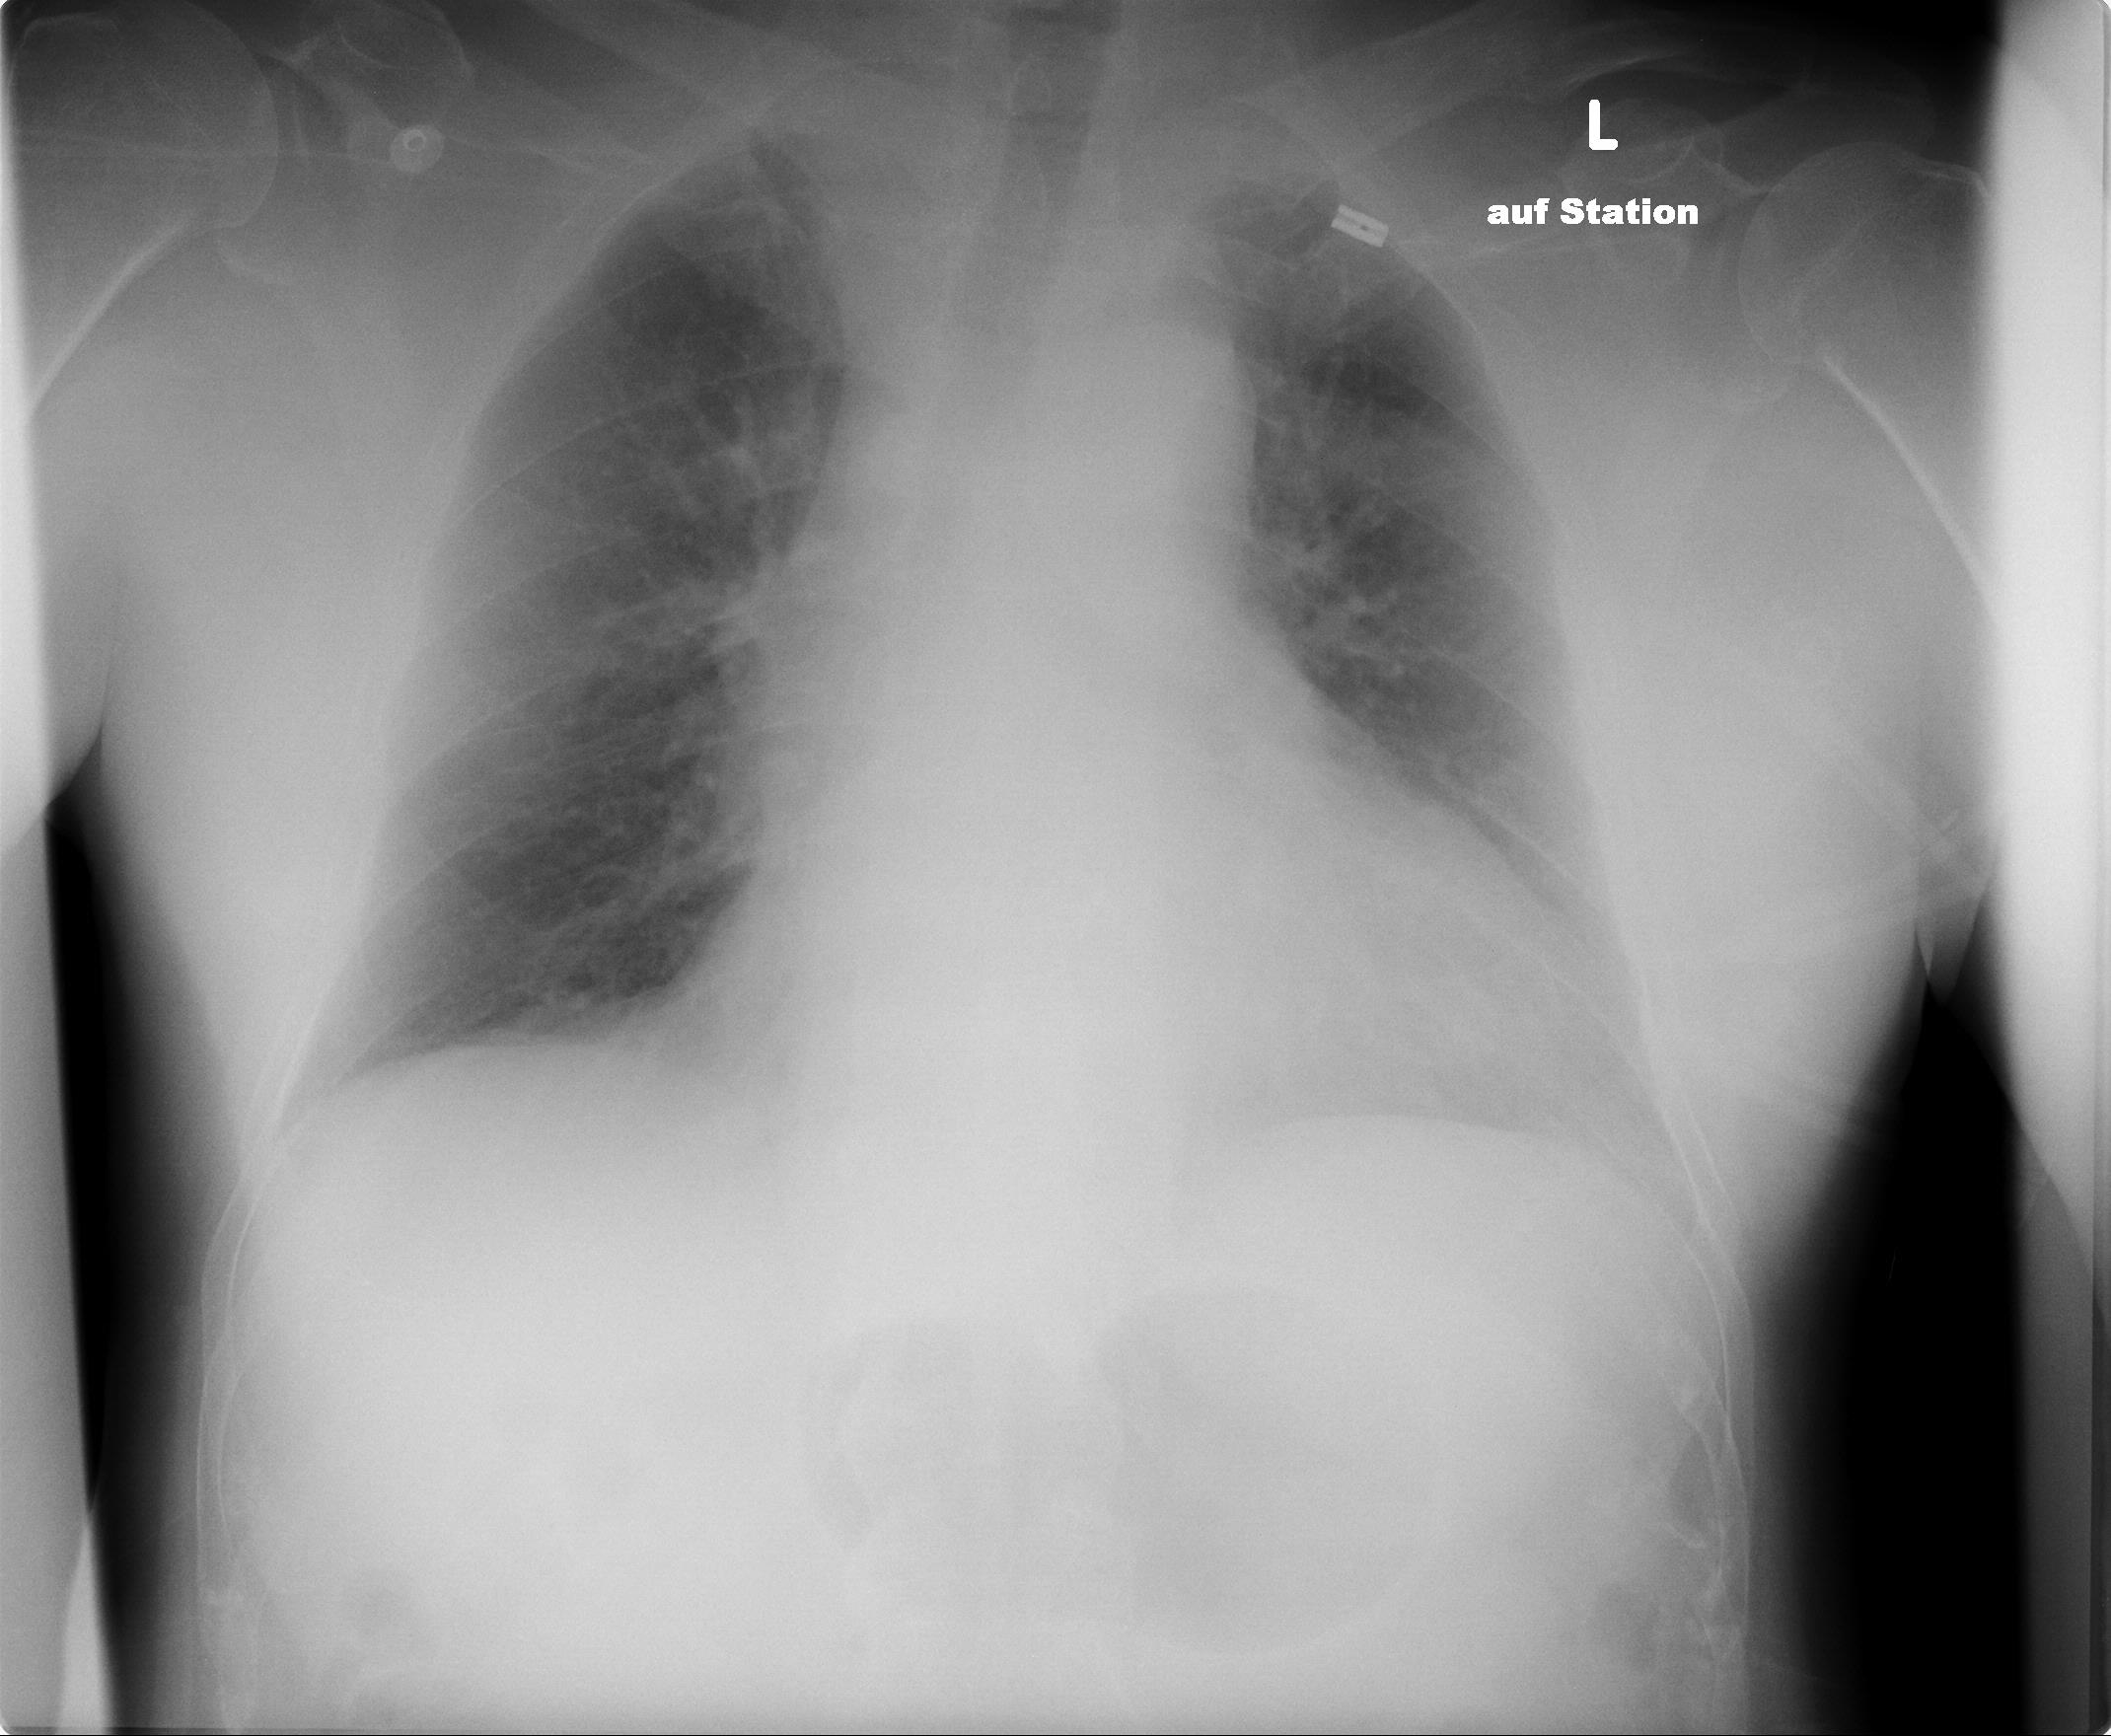

Auch heute noch wird Röntgenstrahlung in vielen Situationen genutzt und ihre Anwendbarkeit weiter erforscht. Am geläufigsten ist "Röntgen" sicherlich als medizinische Untersuchungsmethode von beispielsweise Knochenbrüchen, doch es gibt noch viele weitere Anwendungsgebiete, zum Beispiel der Gepäckscan am Flughafen oder die Untersuchung von Kristallstrukturen.

- Wie sehen Bilder aus, die mithilfe von Röntgenstrahlung erzeugt werden?